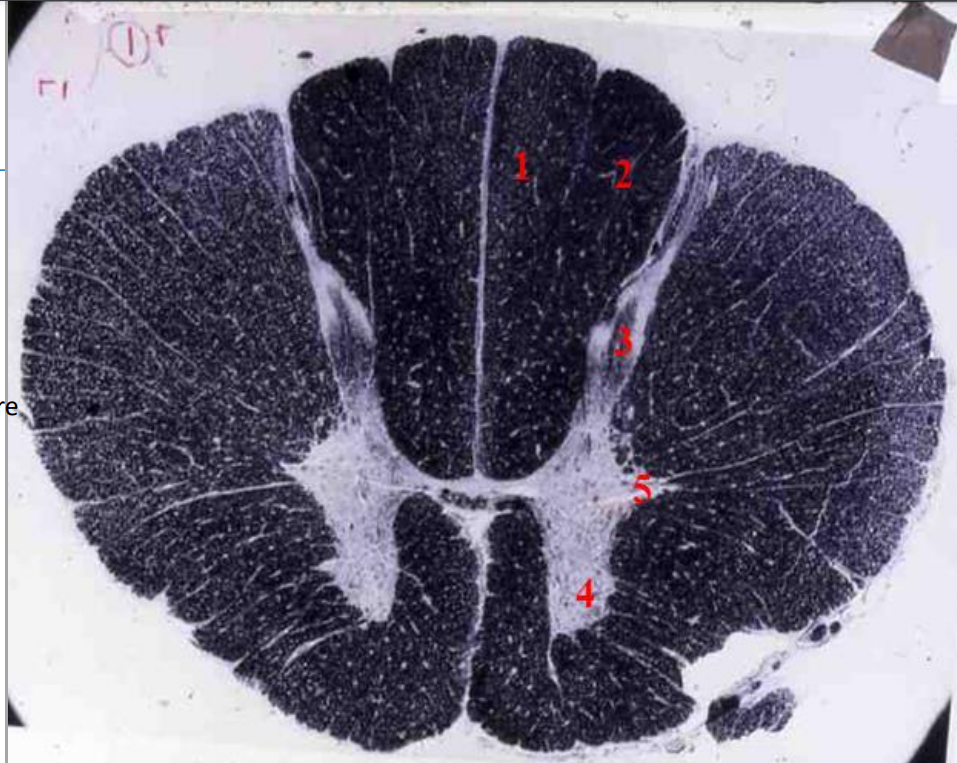

5

Q

identify weigert

A

thoracic cord

- Fibre tracts are larger

- Grey matter is scanty as no limb plexuses

How well did you know this?

1

Not at all

2

3

4

Perfectly

6

fasciculus gracilis

7

fasciculus cuneatus

- dark tracts

- heavilty myelinated

- for fast conduction

8

posterior horn

9

anterior horn

10

lateral horn

- sympathetic neurons